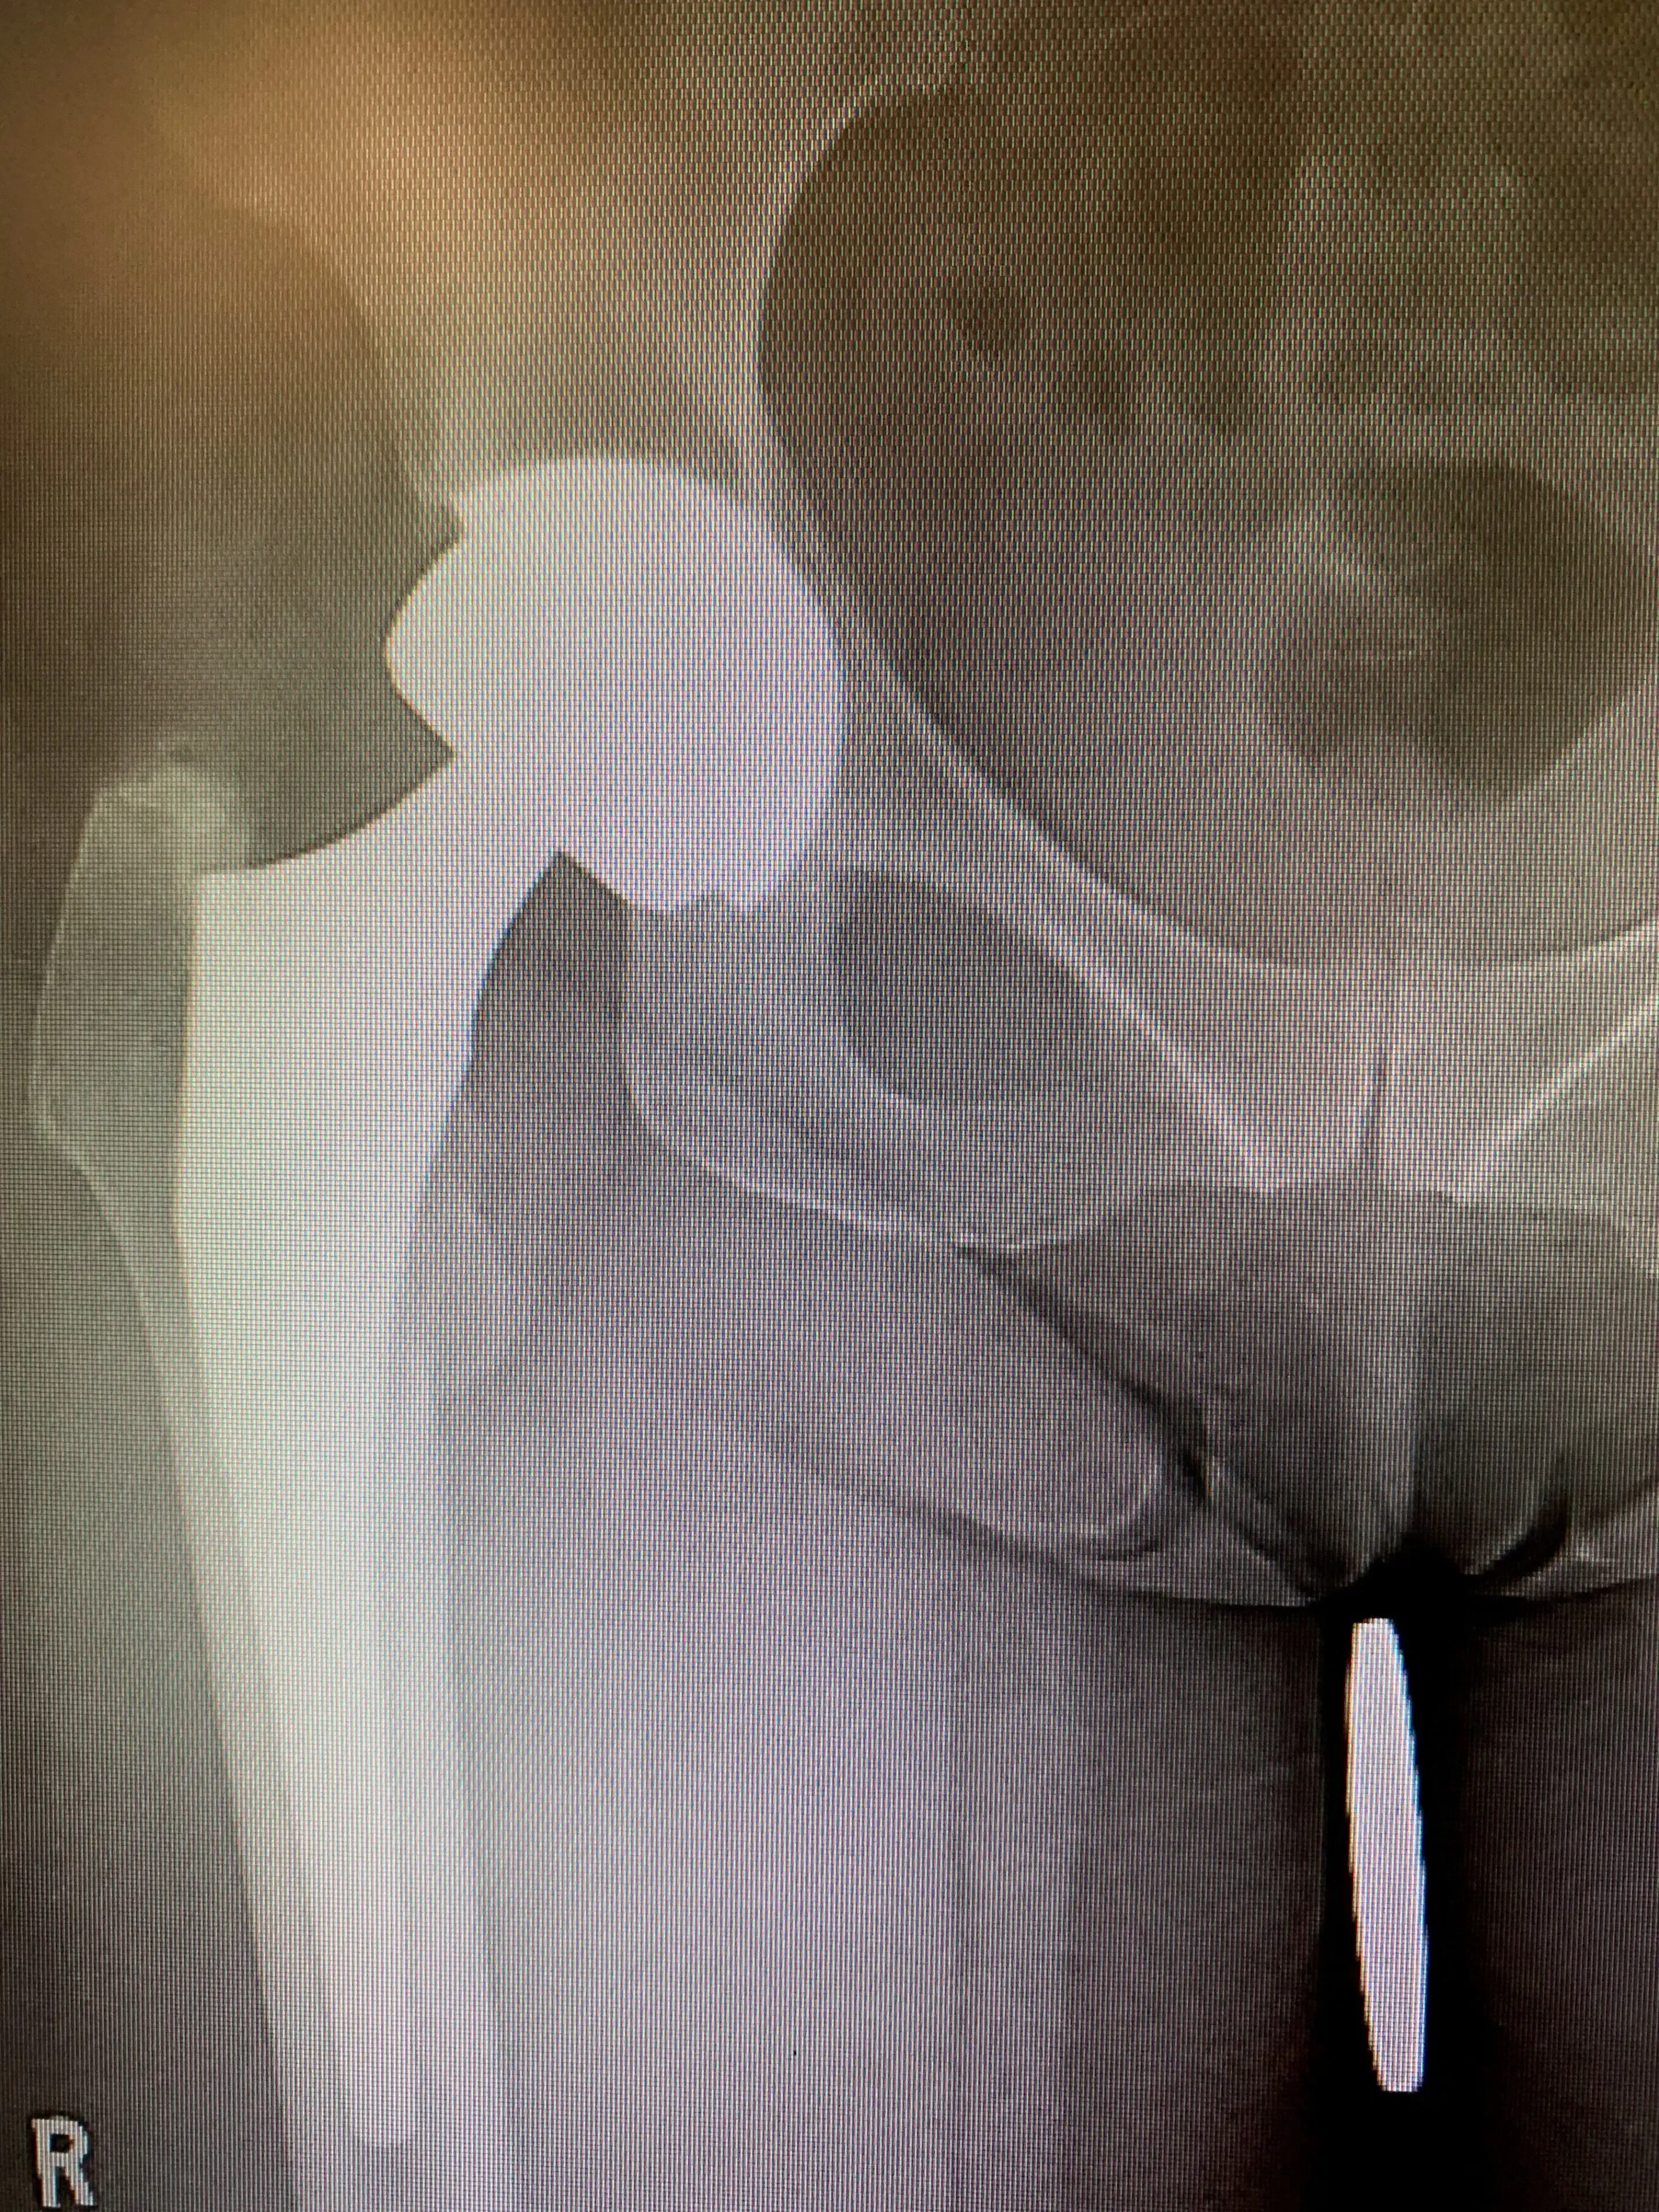

She presented to our clinic with new X-rays that demonstrated asymmetric polyethylene wear in her acetabular component liner. Acquisition of the details of her implants revealed that she did receive an older-generation polyethylene liner, which is known to exhibit signs of wear towards the end of its lifespan.

More detailed examination of her radiographs revealed signs of bone loss around the acetabulum, likely as a result of an inflammatory response generated by polyethylene particles generated from the wear phenomenon. Her femoral component appeared intact with no major issues.

Revision total hip replacement in a 64-year-old. Isolated acetabular component exchange.